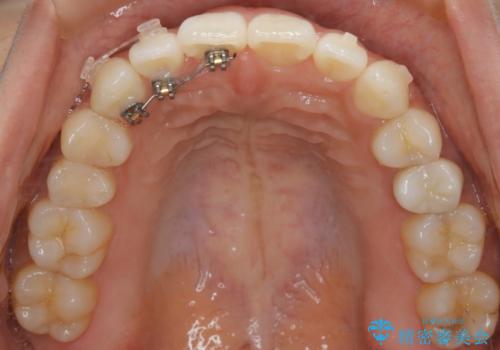

- マウスピース(インビザライン)

ガタつき自体は歯列の幅の拡大やディスキング(IPR)でほとんど解消可能でしたが、噛み合わせのズレは歯の移動が必要だったため、左上にマイクロインプラントを使用し噛み合わせの改善とガタつきの解消を同時に進めるという方針をとりました。